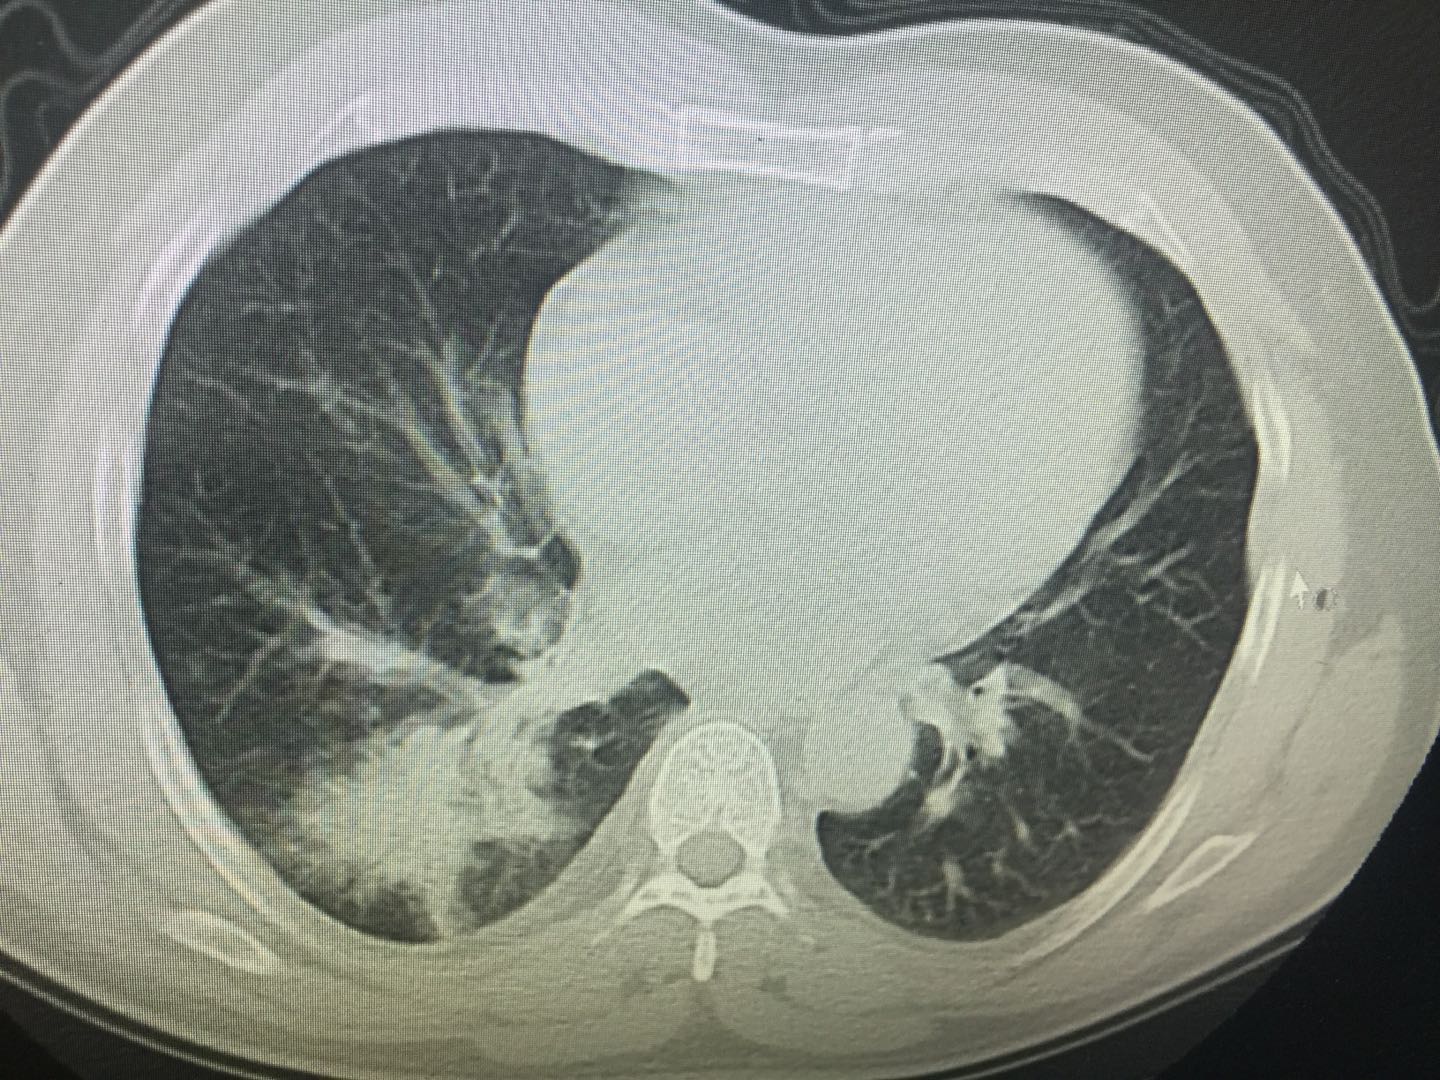

男,73岁.高血压30年,无明显诱因出现咳嗽

白血病肺部浸润ct诊断与鉴别

肺出血-肾炎综合征的影像诊断和临床诊断问题

血行播散性肺结核的影像表现及鉴别诊断| 影像天地